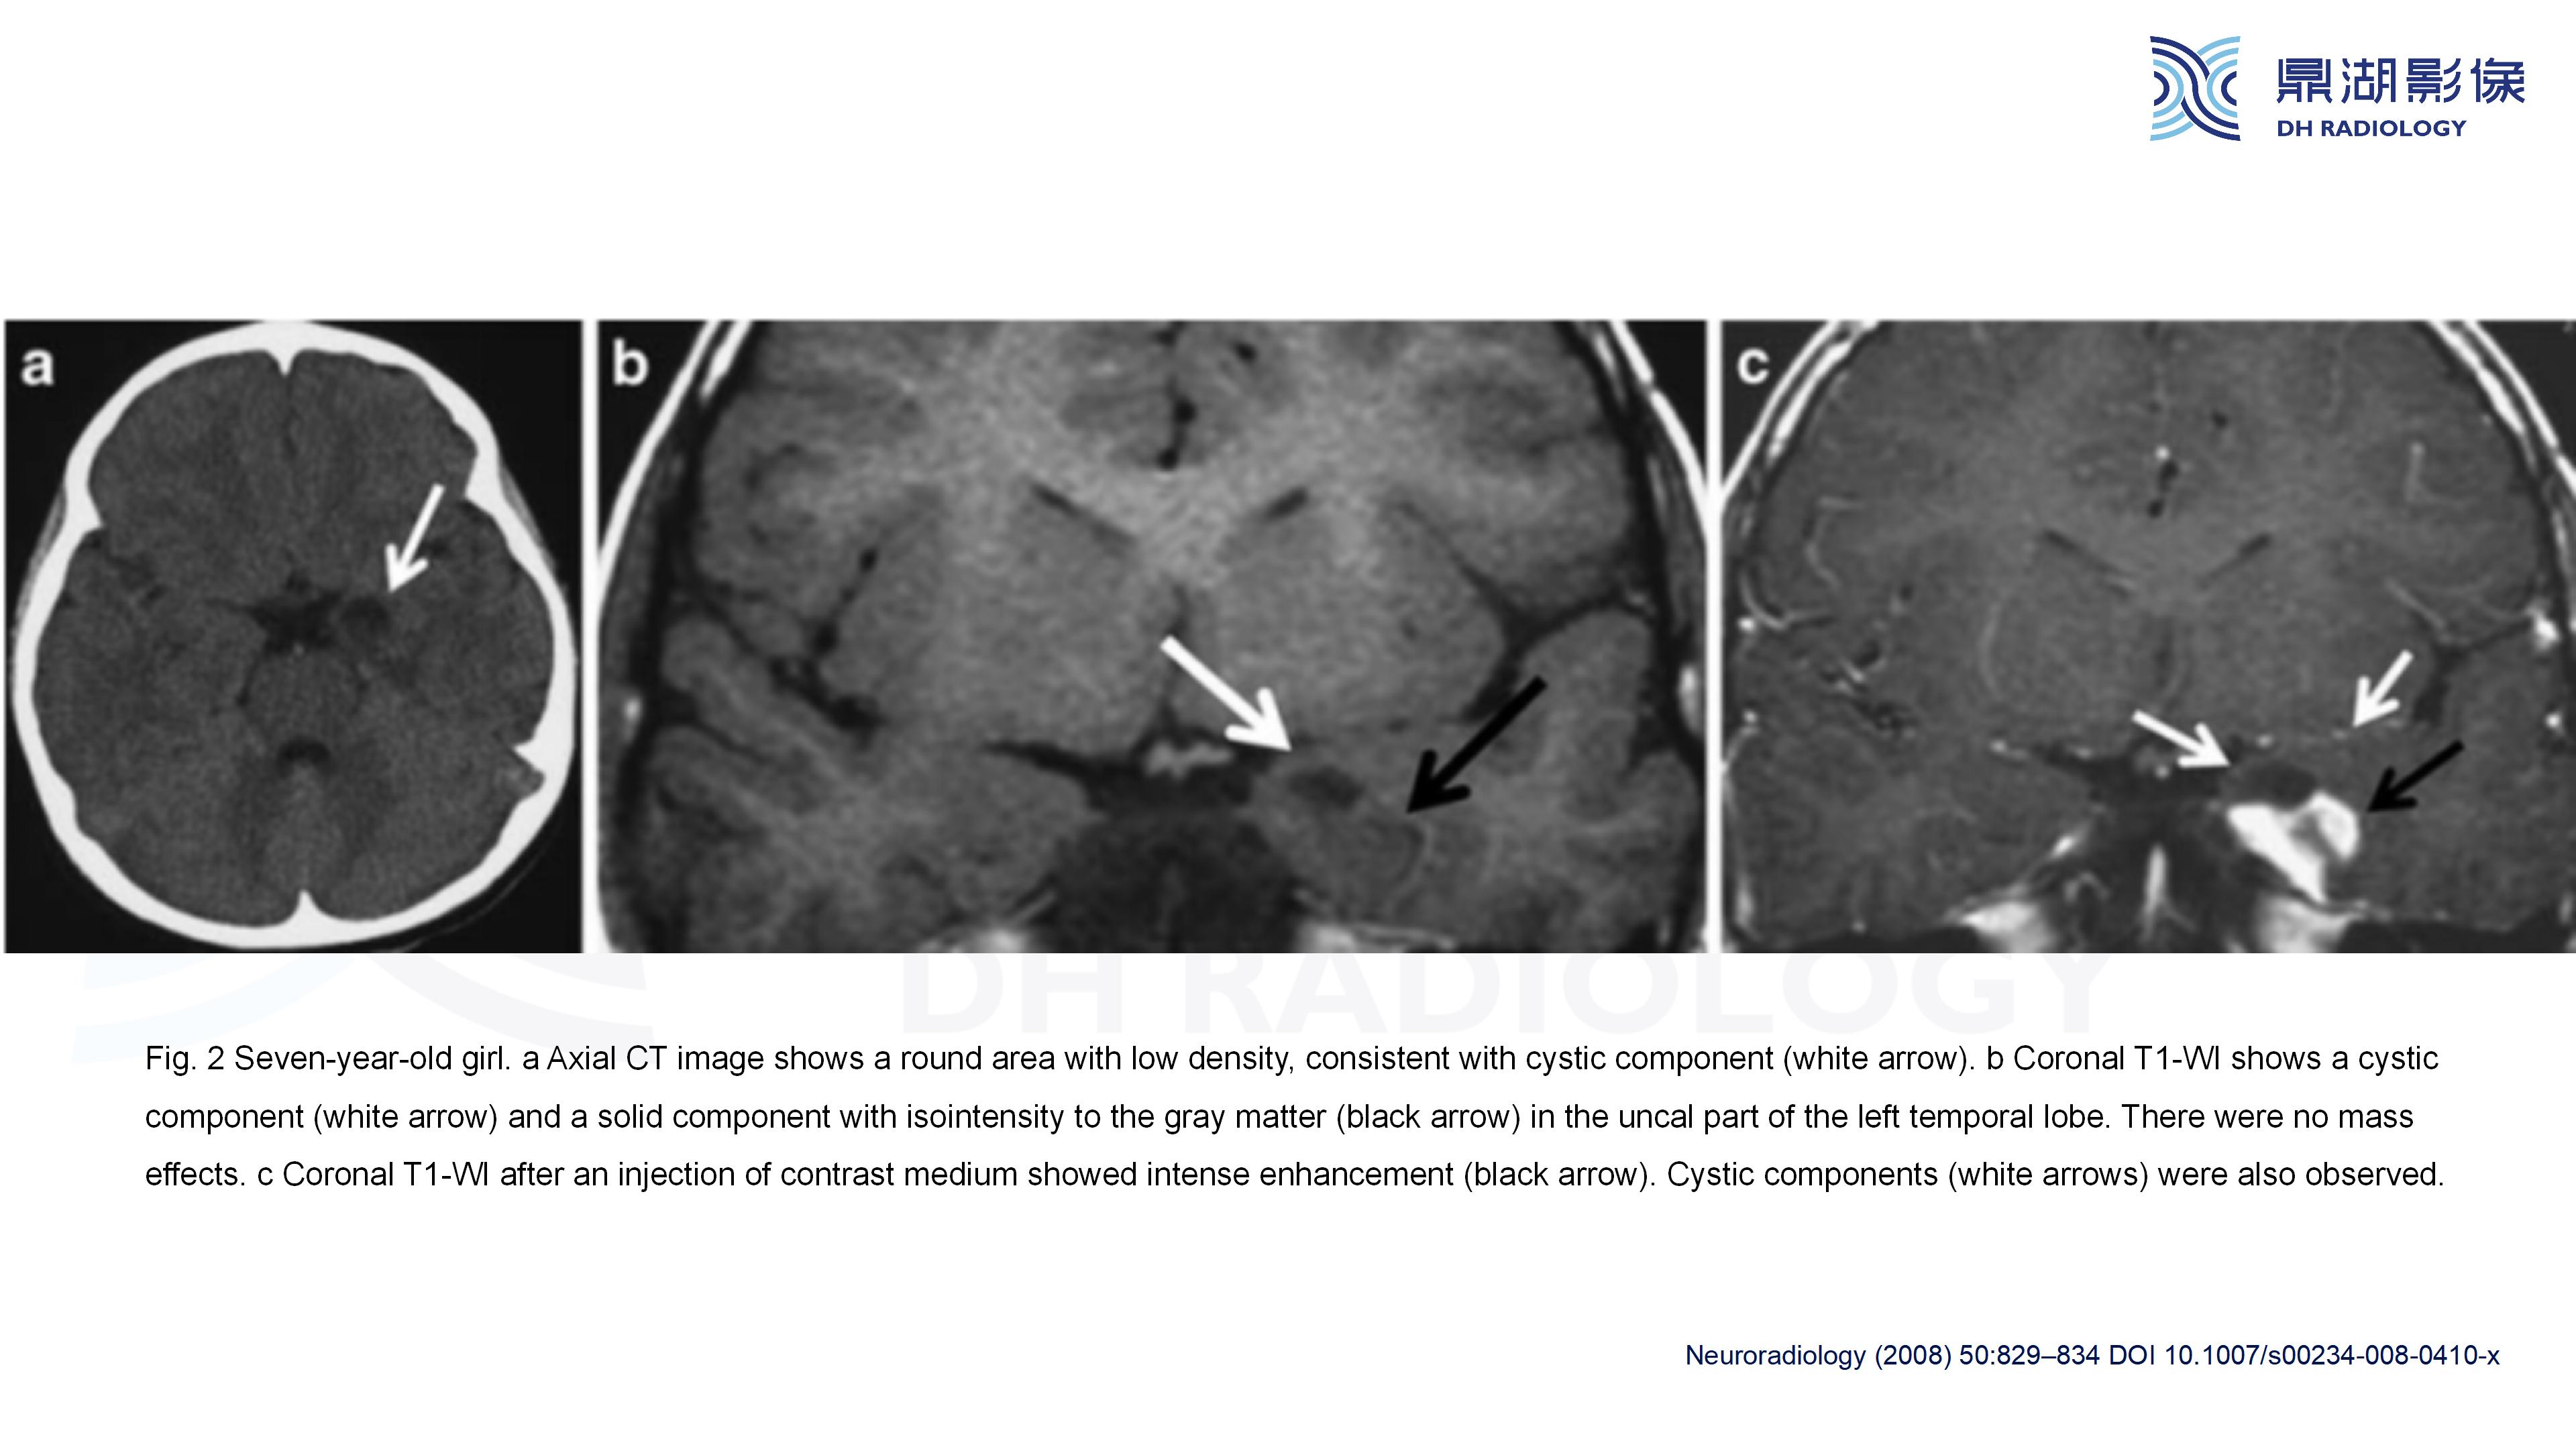

幕上毛细胞型星形细胞瘤(WHO Ⅰ级)